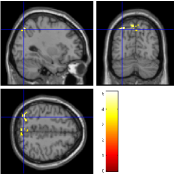

Once the reduced FOV images are available, the proposed pMRI 4D-UWR-SENSE algorithm and its early UWR-SENSE version have been utilized in a final step to reconstruct the full FOV EPI images and compared to the mSENSE Siemens solution. For the wavelet-based regularization, dyadic Symmlet orthonormal wavelet bases [48] associated with filters of length 8 have been used over resolution levels. The reconstructed EPI images then enter in our fMRI study in order to measure the impact of the reconstruction method choice on brain activity detection. Note also that the proposed reconstruction algorithm requires the estimation of the coil sensitivity maps (matrix in Eq. (2)). As proposed in [4], the latter were estimated by dividing the coil-specific images by the module of the Sum Of Squares (SOS) images, which are computed from the specific acquisition of the -space centre (24 lines) before the scans. The same sensitivity map estimation is then used for all the compared methods. Fig. 5 compares the two pMRI reconstruction algorithms to illustrate on axial, coronal and sagittal EPI slices how the mSENSE reconstruction artifacts have been removed using the 4D-UWR-SENSE approach. Reconstructed mSENSE images actually present large artifacts located both at the centre and boundaries of the brain in sensory and cognitive regions (temporal lobes, frontal and motor cortices, …). This results in SNR loss and thus may have a dramatic impact for activation detection in these brain regions. Note that these conclusions are reproducible across subjects although the artifacts may appear on different slices (see red circles in Fig. 5). One can also notice that some residual artifacts still exist in the reconstructed images with our pipeline especially for . Such strong artifacts are only attenuated and not fully removed because of the high level of information loss at .

| mSENSE | 4D-UWR-SENSE | ||

| Axial |  |

|

|

| Coronal | |||

| Sagittal | |||

| Axial |  |

|

|

| Coronal | |||

| Sagittal |